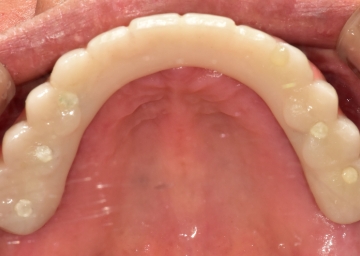

임플란트 : 손 ** 님 (50대)

치아가 있다는게, 아직도 정말 꿈만 같아요.

환자 특징

환자 특징01무치악 상태

환자 특징02수년간 무치악으로 지내심

임플란트가 불가능할것이라

생각하고 내원

위, 아래 6개씩 식립

디지털 풀아치 임플란트